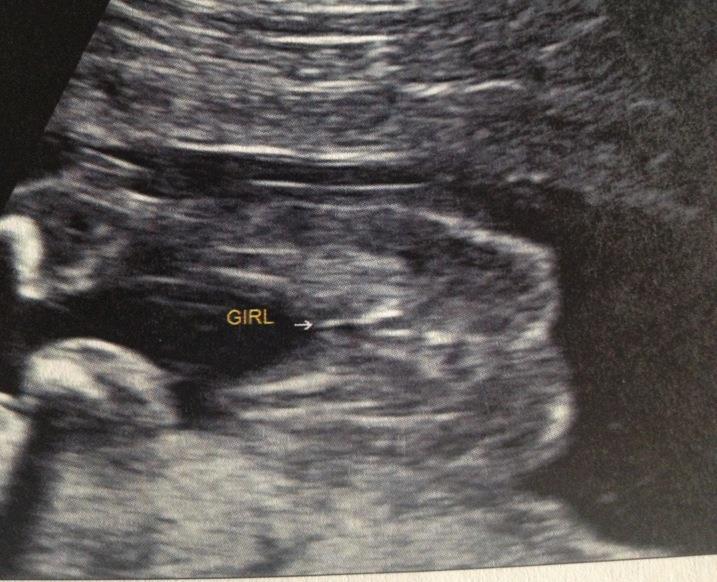

HI LADIES IVE BEEN TOLD ITS A GIRL- DO U AGREE :) Attachment 7780

Looks like a girl, congrats!! How many weeks was the scan?

Scan was 18 weeks and 5 days